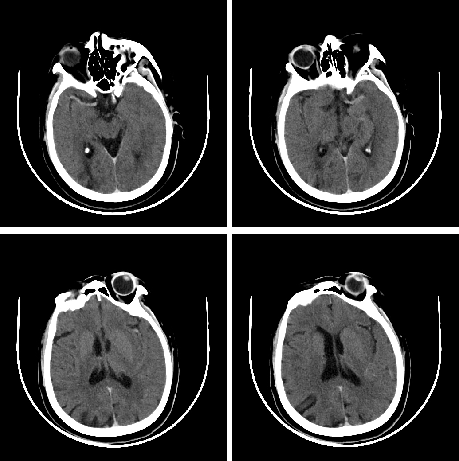

查体BP 160/89mmHg,清醒,双眼左侧凝视位、不可纠正,混合性失语,右侧中枢性面舌瘫,右侧肢体肌力0级,右侧病理征阳性。NIHSS评分18分。随机血糖4.8mmol/L。心电图:正常。颅脑CT无出血及新发梗死灶,多模态CT示左侧大脑中动脉闭塞、左侧大脑半球低灌注。

颅脑CT无出血及新发梗死灶。

多模态CT。